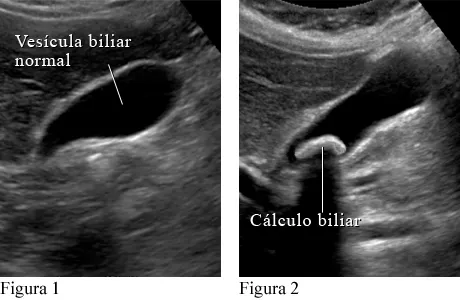

PIEDRAS EN LA VESÍCULA versus GRASA Publicado por José María Armesto Caldeiro el sábado, febrero 15, 2025 Obtener enlace Facebook X Pinterest Correo electrónico Otras aplicaciones Comentarios